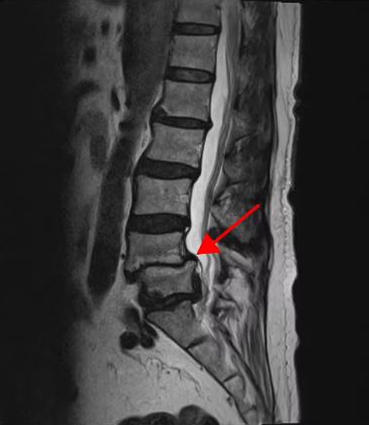

<5-1번 디스크 파열>

이 환자분은 요추 4-5번 오른쪽에 심한 추간공협착증, 2단계의 전방전위증이 있으며, 특히 전방전위증으로 인해 추간공이 매우 좁아져 있습니다. 또 요추 5-1번 왼쪽에 디스크 파열이 있습니다.